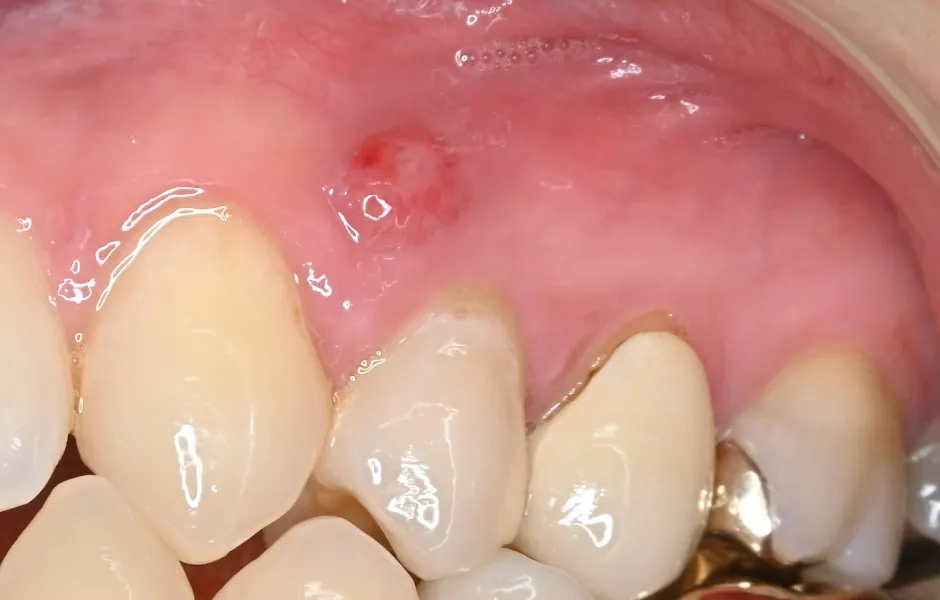

精密根管治療

神経まで進行して炎症を起こしている虫歯に対して行なう治療法になります。感染した神経を取り除き、しっかりと洗浄・消毒し、最後に薬剤を詰めて被せ物を装着します。